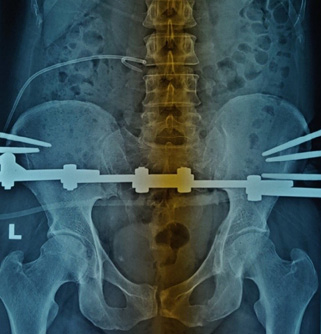

Обзорная урография. Заключение: тень, подозрительная на конкремент, в проекции нижней трети правого мочеточника — 9 мм (рис. 1).

Рис. 1. Обзорная урограмма. Камень нижней трети правого мочеточника. Нефростома справа. Аппарат Илизарова